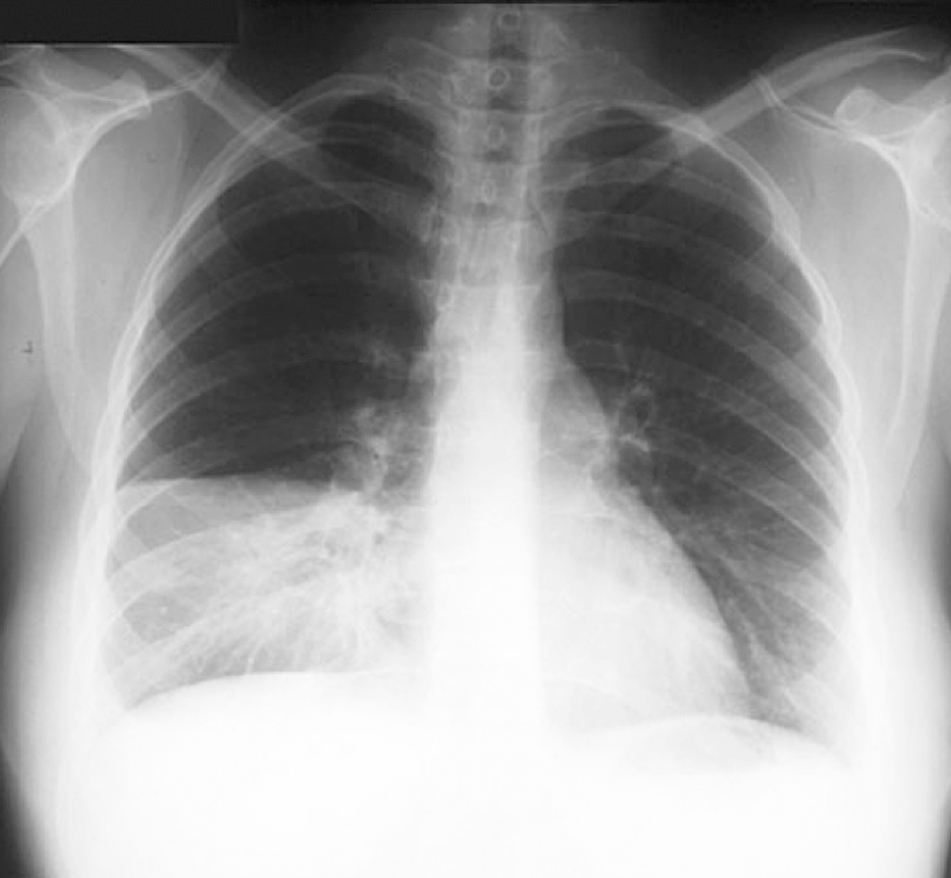

Learn vocabulary, terms and more with flashcards, games and other study tools. Het bloedstolsel ontstaat meestal in de bloedvaten van de benen of het bekken. Predisponerende factoren familiaire predispositie lich.onderzoek x thorax ecg perfusiescan ctscan. Een longembolie bij klachten als (sub)acute dyspneu, pijn op de borst of pijn vastzittend aan de ademhaling, prikkelhoest, hemoptoë risicofactoren: Longembolie (klinische onderzoeken (ct thorax , ventilatie perfusie…: Een longembolie is een bloedprop (stolsel) die is vastzit in een of meer bloedvaten van de long. Partiële of totale pneumothorax, pleuravocht, infiltraten, longoedeem, diffuse longafwijkingen pleuravocht al of niet met hoogstand van het diafragma (dikwijls de enige afwijking bij een longembolie). Veel voorkomende klachten bij een longembolie zijn kortademigheid, pijn bij het ademhalen, zweten en hoesten (soms met het ophoesten van een beetje. Als dit in de longen gebeurt, spreken we van een longembolie. Longembolie wordt behandeld met mediations op basis van de oorzaak, symptomen en eventuele complicaties. National clinical guideline on management of chronic obstructive pulmonary disease in adults in primary and secondary care// thorax. Vanaf het hart vertakt de longslagader zich in steeds kleinere bloedvaten een embolie is de afsluiting van een bloedvat door een bloedstolsel (trombus). Een longembolie is een afsluiting van een longslagader.

Longembolie en dvt zijn verschillende klinische uitingen van dezelfde ziekte. Verminderde bloeddoorstroming in het vaatenstelsel van de longen door een embolus (een stukje weefsel, bloedprop, bacteriemassa of diagnostiek: Atelectasis, pneumonia, interstitial lung diseases, heart failure, pleural fluid, copd, pneumothorax. Een longembolie is een serieuze medische klacht die de dood tot gevolg kan hebben. Longembolie (klinische onderzoeken (ct thorax , ventilatie perfusie…: Predisponerende factoren familiaire predispositie lich.onderzoek x thorax ecg perfusiescan ctscan. Een longembolie is een afsluiting van een longslagader. Tenzij de diagnose op basis van de.